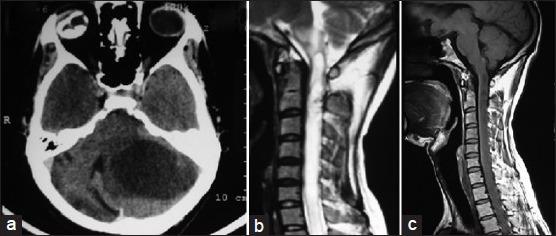

颈髓交界区(CMJ)是脑干向脊髓继续延伸的区域。根据其范围和病理,位于该区域的病变会影响脑干或颈髓或同时影响两者。脑干受累表现为颅神经麻痹,呼吸驱动力下降,长道征象和四脑室阻塞而出现脑积水。颈髓受累与长道征象,脊髓病,霍纳综合征和面部特征有关感觉不足。髓内病变在此区域可以阻碍脑脊液(CSF),并导致延髓空洞症和空洞的形成的流动。

髓内肿瘤在成人中占硬膜内肿瘤的20-30%,在儿童中占硬膜内肿瘤的50%。星形细胞瘤和室管膜瘤等神经胶质瘤占髓内肿瘤的80%。这些肿瘤的大多数向背侧转移并进入四脑室。这通常导致脑脊液从四脑室流出,从而导致脑积水和颅内压升高。少见恶性肿瘤可通过粘着性纤维浸润以累及髓质。在这种情况下,患者可能会出现下颅神经麻痹的特征,以及与上颈髓受累有关的症状。外科手术似乎是较为合适的治疗方法。然而,由于缺乏肿瘤-实质界面,通常很难进行完全的手术切除。利用现代外科技术和仪器,现在已经可以切除这些病变而大大降低了发病率和死亡率。